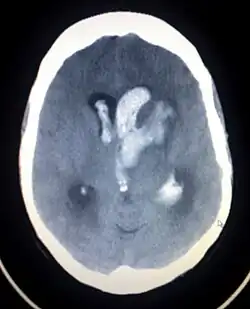

| CT scan showing intracranial hemorrhage | |

Central nervous system (CNS) symptoms of Bonnet–Dechaume–Blanc syndrome are highly dependent on the locations and sizes of cerebral AVMs.[2][5][7] The most common CNS feature is an intracranial hemangioma in the midbrain.[3] Cerebral malformations can result in severe headaches, cerebral hemorrhages, vomiting, meningism, seizures, acute strokes, and progressive neurological deficits due to acute or chronic ischaemia caused by arteriovenous shunting.[3]